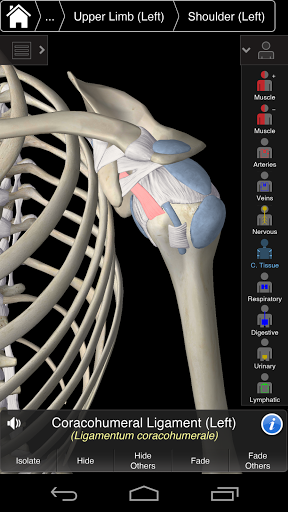

Essential Anatomy 3 represents the latest in groundbreaking 3D technology and innovative design. A cutting edge 3D graphics engine, custom built by 3D4Medical from the ground up, powers a highly-detailed anatomical model and delivers outstanding quality graphics that no other competitor can achieve.

The app represents a unique approach to learning general anatomy. The graphics are unparalleled and make learning, through the use of informative content and innovative features, a rich and engaging experience.

Essential Anatomy 3 is responsive, visually stunning and effortless. The app is fully 3D, meaning that you can view any anatomic structure in isolation, as well as from any angle.

---- Over 4,000 highly detailed anatomical structures

---- Latin nomenclature for each anatomical structure